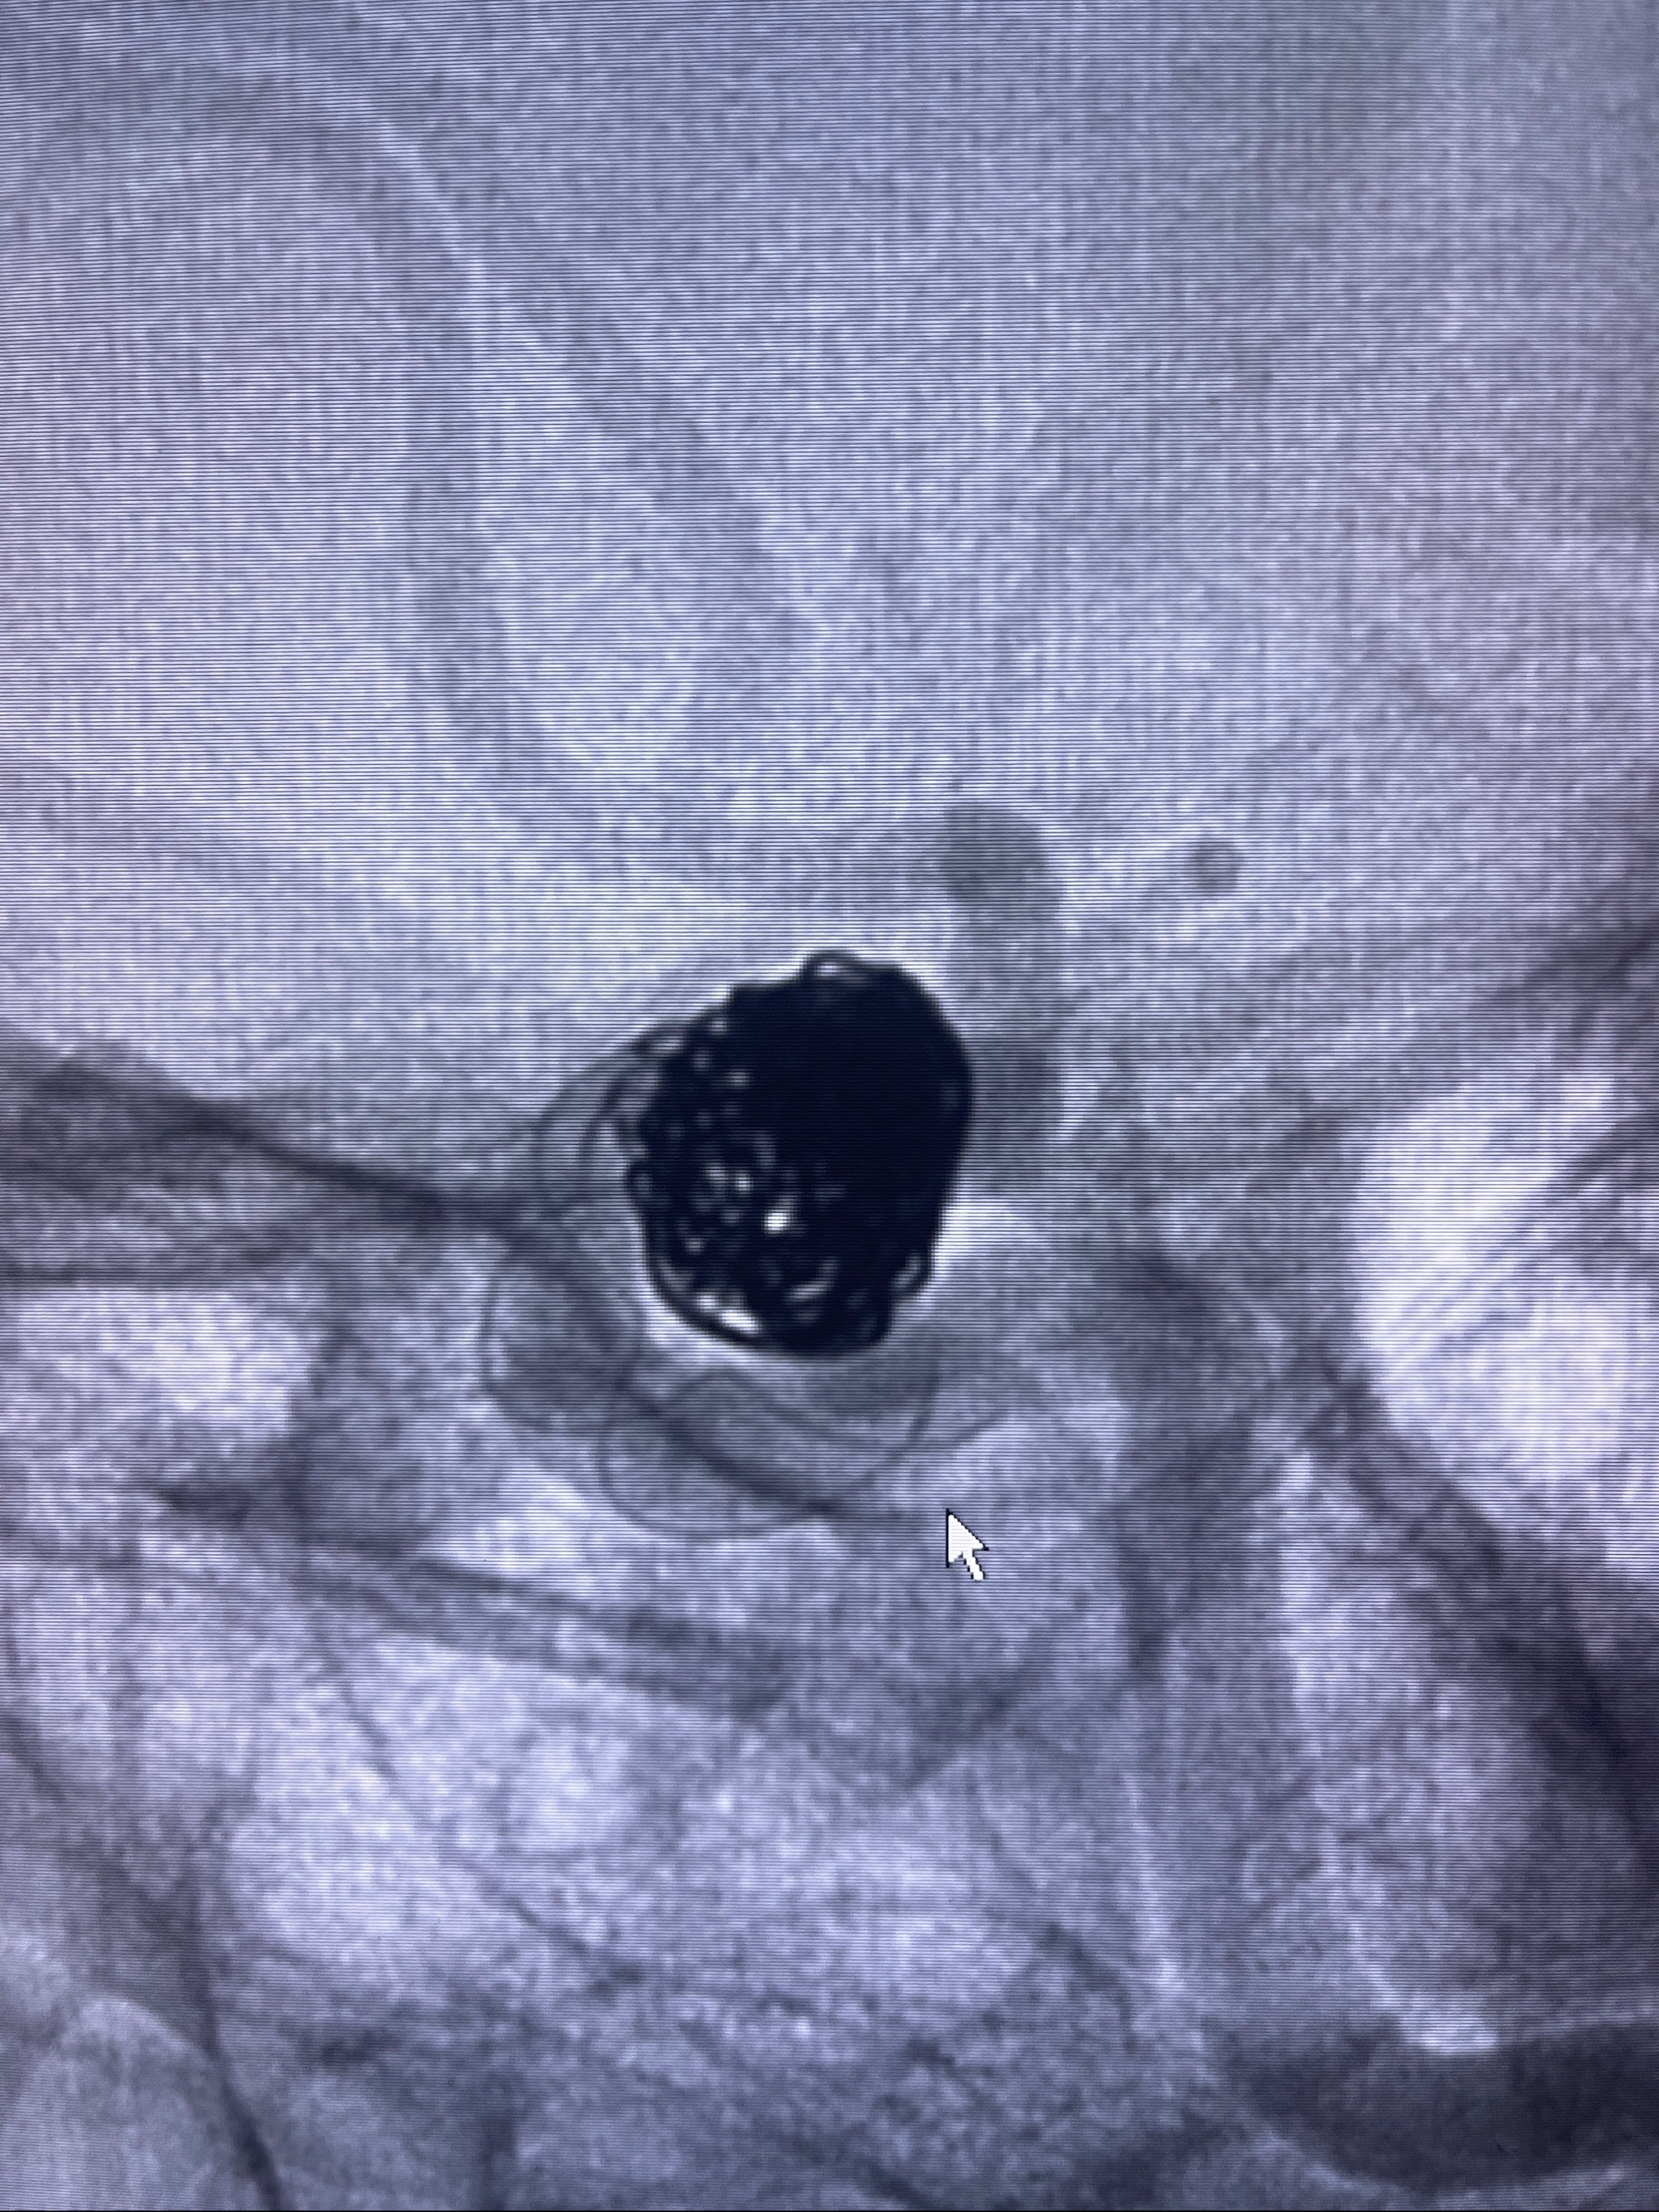

密网支架辅助栓塞

- Tubridge 4.0-20mm密网支架

- 加奇微弹簧圈:7*30/6*20/5*20/2*8

术后3D显示支架贴壁佳